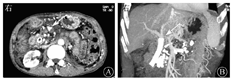

血常规WBC计数为2.74×109/L,RBC计数为3.12×1012/L,PLT计数为84×109/L。血清淀粉酶为112 U/L,胆红素水平正常。肿瘤标志物:AFP正常,CEA为11.07 μg/L,CA19-9为205.50 kU/L,CA125为116.90 kU/L。HBsAg为172.62 mIU/mL,其他乙型肝炎标志物均正常。2016年6月24日,上腹部CT平扫和增强(图1)示:①胆系扩张,胆总管下段有软组织密度影并强化,需考虑占位可能;②胆总管下段多发结石;③慢性胰腺炎并胰管明显扩张;④胆囊结石并胆囊炎;⑤肝硬化;⑥左肾结石,左肾巨大囊肿。MRI和MRCP检查(图2)示:①胆总管下段结石并胆系扩张;②胆总管下段狭窄,需排除占位;③左肾区巨大囊肿。7月2日行内镜下逆行胰胆管造影术(endoscopic retrograde cholangiopancreatography,ERCP),内镜显示食管静脉曲张(重度),胆管造影示胆总管中段明显狭窄,狭窄处长约2.0 cm,狭窄以上肝外胆管扩张,术中胆管腔内超声(intraductal ultrasonography,IDUS)检查狭窄处胆管未见明显异常,造影未见明确结石影,沿胆总管导丝置入覆膜金属支架于狭窄处。7月7日泌尿系统多普勒超声检查示左肾窝异常回声团块,考虑左肾囊肿可能。7月9日计算机断层扫描泌尿系统延时成像(computed tomographic urography,CTU)(图3)示:左肾区囊性病灶未见造影剂进入,提示假性囊肿形成可能性大。7月20日肝脏静脉血管造影(computed tomographic venography,CTV)(图4)示:肠系膜上静脉血栓形成,门静脉主干起始处闭塞,门静脉海绵样变性。8月1日复查CT增强(图5)示:①肝内胆管扩张、胆总管内置管术后改变。②慢性胰腺炎;胰尾囊肿引流术后,囊腔内积气。

消化科吕农华主任医师:患者病情复杂,现已先后明确了胆总管狭窄的性质、左侧腹膜后囊肿的性质并进行了相应的处理。目前要讨论的是门静脉高压的问题。患者有重度食管静脉曲张,结合患者血常规三系减少合并脾功能亢进的表现,CT检查显示门静脉主干起始闭塞,门静脉海绵样变性,首先考虑肝前性门静脉阻力增加导致的门静脉高压,门静脉闭塞原因考虑与胰腺炎性反应、囊肿压迫门静脉导致血流缓慢有关。其次,患者有肠系膜上静脉血栓,也可移行致门静脉引起闭塞。国外一项前瞻性研究对266例慢性胰腺炎患者进行了超声检查和血管造影或CT扫描,结果显示主要内脏静脉闭塞的发生率为13%,其中脾静脉、门静脉和肠系膜上静脉闭塞分别为8%、4%和1%[9]。患者有长期饮酒史,CT检查提示肝硬化,但肝脏体积并不缩小,酒精性肝硬化导致的肝内型门静脉高压的可能性较小。最后,胰腺假性囊肿也可压迫脾静脉导致左侧门静脉高压,但CT检查未见脾静脉狭窄或闭塞,内镜未见胃底静脉曲张,胰源性门静脉高压可能性小;可行经颈静脉肝内门体静脉分流术(transjugular intrahepatic portosystemic shunt,TIPS)门静脉和肠系膜上静脉取栓+溶栓术进行治疗,必要时放置支架,患者出血停止后还要考虑抗凝治疗。

影像科余晨主治医师:按照血流受阻的部位,门静脉高压可分为:①肝前型,常见病因有门静脉血栓形成、门静脉海绵样变性、胰源性门静脉高压等;②肝内型,常见病因有肝炎后肝硬化、特发性门静脉高压、血吸虫病性肝硬化等;③肝后型,常见病因有巴德-吉亚利综合征(Budd-Chiari syndrome)、右心力衰竭等[10]。其中,肝炎后肝硬化所致的肝内型门静脉高压在临床上最为常见,然而本例患者乙型肝炎标志物检查中仅HBsAg为阳性,基本可排除肝炎后肝硬化所致的肝内型门静脉高压的可能。肝脏CTV显示肝静脉和下腔静脉肝段显示清晰,无明显狭窄,基本可以排除巴德-吉亚利综合征所致的肝后型门静脉高压。肝脏CTV显示肠系膜上静脉血栓形成,门静脉主干起始处闭塞,则表明此例患者的门静脉高压为肝前型。当门静脉主干和(或)分支完全或部分阻塞后,机体通过自身代偿机制根据阻塞部位可于门静脉主干和(或)分支周围、肝门区和肝十二指肠韧带处形成大量的侧支循环,由于这些血管在大体标本切面呈海绵状血管瘤样的改变,故称门静脉海绵样变性。由于患者还有慢性胰腺炎的背景,至于其是否为胰源性门静脉高压,则要看其是否符合胰源性门静脉高压的定义。胰源性门静脉高压是因胰腺疾病导致门静脉系统的属支(主要是脾静脉)梗阻、血液回流障碍而引起的区域性门静脉系统压力升高[11]。该例患者的脾静脉显示清晰,无明显管腔狭窄和阻塞的征象,因此该例患者的门静脉高压病因基本可确定为是门静脉血栓所致的肝前型门静脉高压。

血管外科邓军主治医师:推测该患者门静脉高压与门静脉主干闭塞有关,闭塞原因以血栓形成的可能性大。对于新发生的门静脉血栓,可直接采用门静脉溶栓治疗;对于已经机化的血栓,单纯溶栓效果欠佳,而手术取栓创伤大,由于患者高龄,所以暂不考虑手术治疗。介入方法可采用TIPS门静脉取栓,也可采用经皮经肝门静脉成形支架置入开通术,用支架维持门静脉入肝血流通畅。不论是否放置支架或保守治疗,均建议服用适量抗凝药物,这对长时间维持支架血流通畅和恢复患者的肝功能有积极的意义。口服抗凝药物方案有利伐沙班片或华法林,后者需每周监测PT(目标值为30 s)、凝血酶原时间-国际标准化比值(prothrombin time-international normalized ratio,PT-INR)(目标值为2~3),同时可给予低分子肝素4 000 U皮下注射,每12 h 1次。